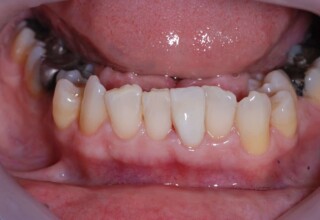

Αποκατάσταση διαστημάτων μεταξύ κεντρικών και πλαγίων τομέων

Τα διαστήματα έχουν δημιουργηθεί κυρίως λόγω των στενών πλαγίων. Μετά την ολοκλήρωση της ορθοδοντικής θεραπείας τα διαστήματα “έκλεισαν” με την τοποθέτηση δύο αποκαταστάσεων σύνθετης ρητίνης.